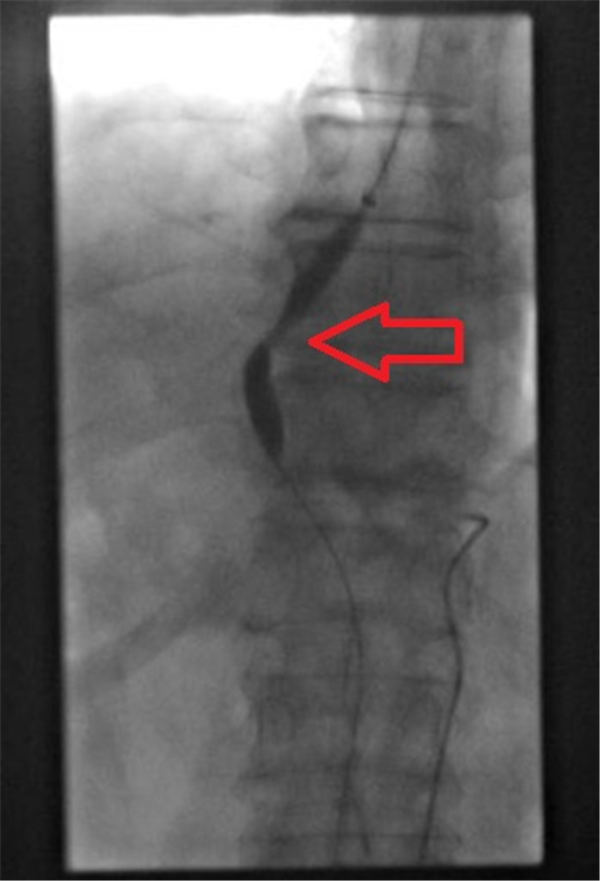

经过周密的准备计划,成功为老人实施了从颈内静脉插管到肝静脉穿刺门静脉。后经门静脉造影,可见:门脉增粗,食管胃底静脉曲张(如下图,绿色箭头为门脉主干、黄色箭头为门脉内血栓、红色箭头为连接食管胃底静脉曲张的胃冠状静脉,弹簧圈栓塞胃冠状静脉栓塞)。

置入支架(红色箭头之间)后造影,显示:门脉血液经支架回心,胃冠状静脉不显影。

TIPS完成后,再行肝癌栓塞化疗。肝动脉造影发现肝内肿瘤染色(如下图红圈所示)。